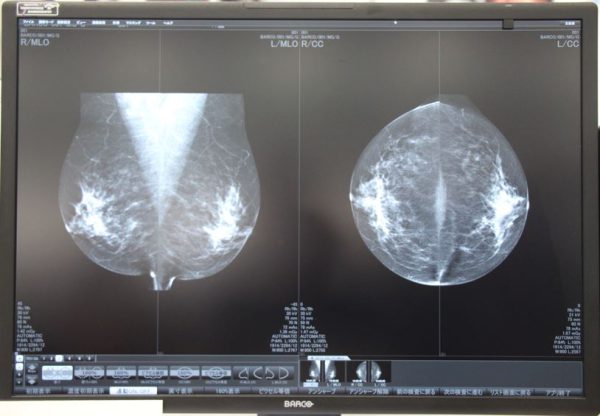

Nio Fusion 12MP

「Nio Fusion 12MP」は、30.9インチのワイド画面を採用し、多様なモダリティ画像の1画面表示に対応したFusionコンセプトのディスプレイで、日本乳がん検診精度管理中央機構より適合モニタとしての認定を受けている。2台のワークステーションを切り替えて表示できるKVM機能も搭載。

Nio Fusion 12MP(MDMC-12130)